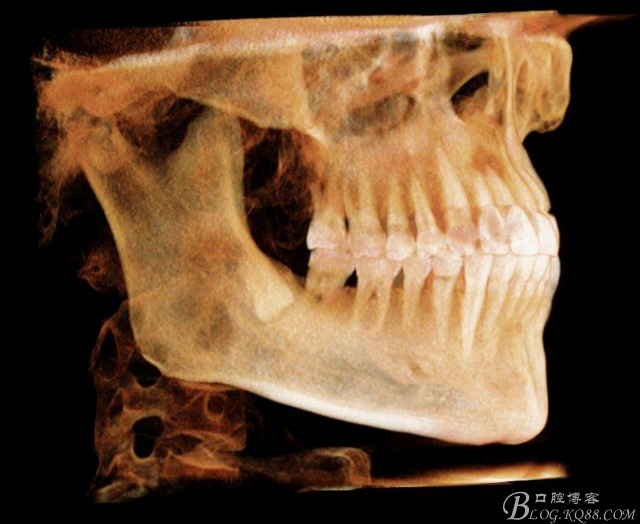

二、術(shù)前CBCT影像:

圖5. 48的三維視圖